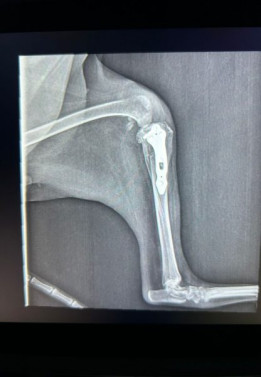

Max Move Aero DDR

Max Move Aero DDR / Foto: Divulgação

O diferencial do Max Move Aero DDR está em sua capacidade de realizar avaliações radiográficas em movimento, algo impossível para os aparelhos convencionais. Essa tecnologia possibilita uma análise morfofuncional das estruturas estudadas, permitindo observar articulações, músculos, ossos e outras regiões anatômicas em pleno funcionamento.